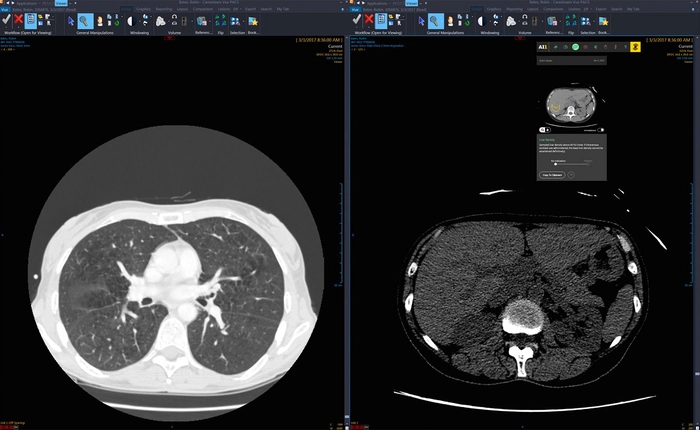

Khám phá -

30/10/2017 | 07:34

Công cụ này có thể thông qua các hình ảnh X quang, MRI, CT scan... để chẩn đoán ra các bệnh tiềm ẩn cho bệnh nhân.